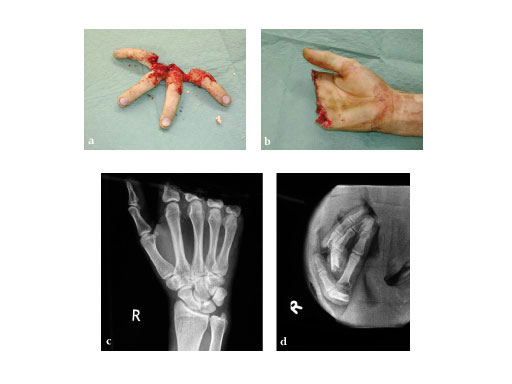

30-year-old male, work accident with buzz-saw.

Fig 1ad: Preservation of the short base of the proximal phalanx for the extremly important flexion of the metacarpophalangeal (MP) joint.